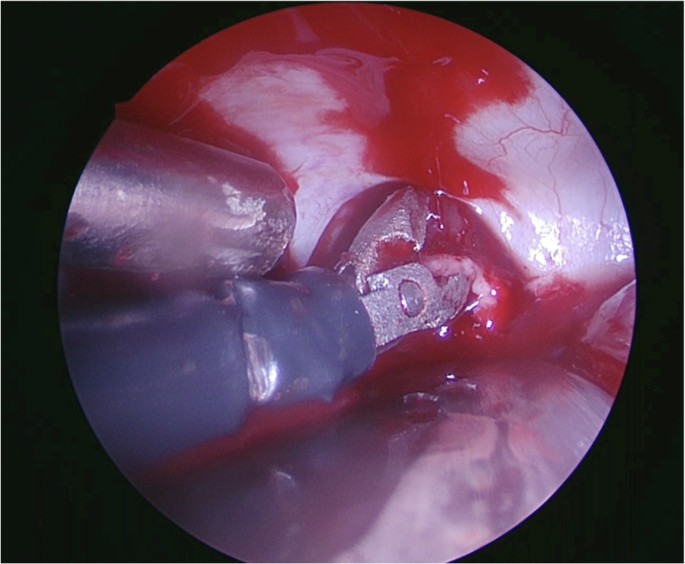

Figure 4 illustrates us of the forceps. The forceps was deemed easier to use compared to the dissector, but harder to use compared to the curette across all approaches (Fig. 2). The forceps performed best in the transparietal approach and worst in the subfrontal approach. Feedback included that they “work as expected, force was correct, but difficulty related to the narrow opening and not from [the] instrument”, “It could potentially be easier to push for a release”, “slightly too sharp” and that “the head was tilted down when fully closed”. The usability of the forceps was considered easy for manipulating arachnoid tissue (albeit not sharp enough), blood vessels and brain tissue.